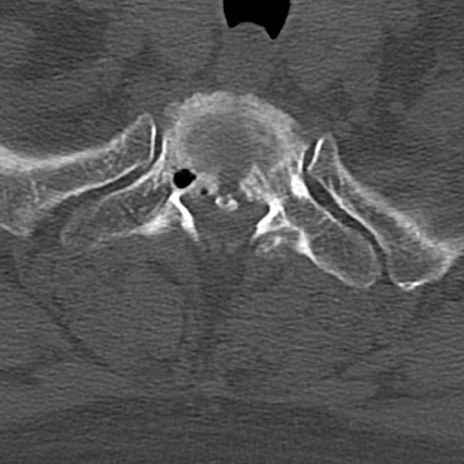

頚椎CT

横断像